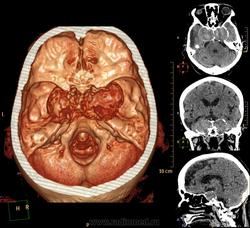

А контраст почему не делали? Больше похоже на тромбированные аневризмы

Неужели такие аневризмы? Бывает же! А сканы с контрастом есть?

Макроаденома гипофиза с интра-эндо-супра-и латероселлярным ростом,инвазией кавернозных синусов и зрительной хиазмы.

В первую очередь подумала бы о менингиоме бугорка турецкого седла или передних наклоненных отростков. Дифференцировала бы с краниофарингиомой но смущает форма.

Да простят моё нахальство уважаемые специалисты КТ. Я вижу тут огромные инкапсулированные узлы расположенные почти симметрично справа и слева от турецкого седла, которое разрушено узлом поменьше. Латеральные злы продавливают дно средней черепной ямы. По-видимому, здесь доброкачественная опухоль типа «аденома», исходящая из гипофиза и давно растущая. Обызвествление есть не только в капсулах узлов, но и в их толще (очаговое). При таких размерах узлов и косных разрушениях, нет сомнения, пострадали и зрительные нервы.

Цифровых и плёночных доказательств на руках нет. Опухоль диагностирована в 2004 году, размером "с вишню", дебютировала птозом века правого глаза, умеренной головной болью в лобной области слева и постепенным снижением зрения, катаракта. Пациентка с трезвом уме и превосходной памяти (на мой субъективный взгляд))). В выписке результаты КТ, МРТ: неоперабельная опухоль селлярно-параселлярной области с прорастанием кавернозных синусов, аневризма сифона внутренних сонных артерий. Цитологию НЕ брали.

Не совсем понятно, опухоль + аневризма или как?

Да, опухоль, в толще которой аневризма сифона ВСА. Причем с обеих сторон.

Аневризмы с обеих сторон или опухоль?

И то, и другое. Доказать без контрастирования не могу. Когда сама впервые увидела, анамнеза не знала, подумала о двусторонней аневризме. И не угадала.

Насчет опухоли у меня большие сомнения. То что седло растянуто, еще не показатель. Седло увеличивается в размерах даже при гипертонии,а тут такие аневризмы. Самой опухоли не видно, в просвете турецкого седла медиальные полюса аневризм. Ну впрочем не так это важно, интерес чисто теоретический, да и верификации видимо не будет. Спасибо большое за демонстрацию.

Случай-таки не верифицированный. Сочетание опухоли с аневрзмами - это очень странно. Боюсь, тут какая-то путаница.

На мой взгляд, случай требует более внимательного рассмотрения и относительно "готового диагноза", и относительно "неоперабельности".